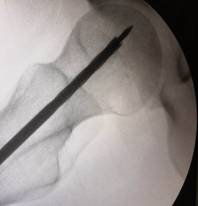

經(jīng)過術(shù)前與麻師團(tuán)隊(duì)詳盡的討論及預(yù)案制定后,手術(shù)醫(yī)師首先為吳先生實(shí)施雙側(cè)股骨頭壞死髓芯減壓,即打開一個(gè)像筷子大小的“隧道”孔后,再通過“隧道”將分離的血小板注射進(jìn)吳先生骨頭壞死區(qū)域。整個(gè)手術(shù)僅抽取了80毫升血液,耗時(shí)數(shù)十分鐘,術(shù)后三天患者出院。

術(shù)中,為患者打通“隧道”,注入血小板